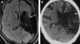

Cerebral atrophy in childhood